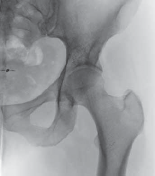

3. Plain radiographs, including anteroposterior (AP) views of the pelvis and a lateral cross-table view, should be obtained.

4. Acetabular orientation (eg, anteversion, retroversion) and the depth of the acetabulum (eg, coxa profunda, protrusio) are assessed on the AP pelvic view (

FIG 2A

).

5. For proper assessment of the acetabular shape and version, the central x-ray beam must be centered about 2 cm above the symphysis pubis.

1. Any rotation to the right or left must be avoided, because this can lead to over- or underestimation of acetabular retroversion.

6. The lateral cross-table view shows the anterior contour of the head–neck junction with offset deficiencies or anterior bumps (

FIG 2B

A B FIG 2•A.

Standardized AP pelvic view, showing bilateral acetabular retroversion. On the left hip the anterior (

dotted line

) and the posterior (

full line

) are outlined and form a figure-8 sign.

B.

On the lateral cross-table view, however, an important anterior bump becomes visible.